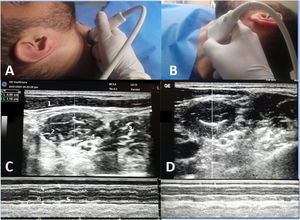

An experienced operator (AE), who completed more than 50 similar examinations before the commencement of the study, performed the diaphragmatic and scalene muscle ultrasound. The operator was blinded to the clinical data and not involved in the weaning process. Examinations were conducted using the Versana Essential device (GE Medical Systems Co., Ltd., China) at mid-trial (15 min after initiation of SBT) while the patient was semi-sitting. For scalene muscle evaluation, a high-frequency linear transducer (L6-12-RS, 4–16 MHz) was placed horizontally at the level of the cricoid cartilage with the neck rotated to the opposite side; at this point scalenus anterior muscle can be visualized clearly below the lateral border of sternocleidomastoid muscle, brachial plexus between the anterior and middle scalene muscles, and finally internal jugular vein below scalenus anterior muscle. The M mode was then switched on in the middle of the muscle with the sweep speed adjusted to a minimum to allow multiple breaths to be obtained on the same screen (Figs. 1, 2). Inspiratory and expiratory thickness was measured as an average of 3 breaths; subsequently, the thickening fraction was calculated as (inspiratory thickness – expiratory thickness)/expiratory thickness and expressed as a percentage. The diaphragmatic examination was in concordance with a recent consensus statement23 and current literature9,10,17 using a curved probe (4C-RS, 2–5 MHz) placed at the 10th or 11th intercostal at the right anterior axillary line and the left midaxillary line for each hemidiaphragm assessment, patient was then asked to take maximum breath, subsequently M mode was switched on to measure diaphragmatic excursion as an average of 3 successive breaths. The main outcome variable in this study was the ability of the scalenus anterior thickening fraction (SA-TF) to predict failed weaning (failed SBT and reintubation); other outcomes were the ability of RSBI to predict weaning outcomes, and finally, the correlation between diaphragmatic excursion and scalene thickening fraction.

Scalenus anterior thickening.

A-probe position for right side examination, B-probe position for left side examination.

C-ultrasound view of right scalenus anterior, D-ultrasound view of left scalenus anterior.

1-sternomastoid muscle, 2-anterior scalene muscle, 3-middle scalene muscle.

4-brachial plexus, 5-inspiratory thickness, 6-expiratory thickness.